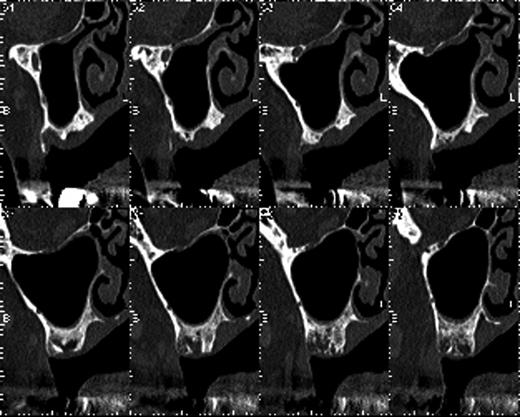

The patient used a jaw prosthesis with clasps over the remaining left maxillary teeth. However, these teeth were not strong enough to support a large jaw prosthesis that would cover the right maxillary defect, and residual teeth were missing. The patient sought implant treatment in the left maxillary molar region. However, computed tomography (CT) revealed that the bone mass of the left molar region was inadequate for implantation of these fixtures (Fig. 2). We performed the sinus-lift procedure under local anesthesia. The soft tissue from the canine region to the molar tooth region was incised and elevated to expose the underlying lateral wall of the left maxillary sinus. A 12 × 5 mm window was created in the bone of the maxillary sinus anterior wall with a piezoelectric instrument to expose the underlying Schneiderian membrane, which is the lining of the maxillary sinus cavity. Through careful instrumentation, the membrane was carefully peeled from the inner aspect of the sinus cavity (Fig. 3a). No damage to the membrane of the maxillary sinus was present. The newly formed space within the bony cavity of the sinus inferior to the intact membrane was grafted with artificial bone, and artificial bone was placed on the alveolar crest to raise the alveolar crest (Fig. 3b). The gingival flap was replaced and sutured to complete the sinus-lift procedure. There was minimal hemorrhage during the operation, and hemostasis was adequate. There was insignificant facial swelling immediately after the operation.

The bone mass in the left molar region was inadequate for implantation of fixtures.